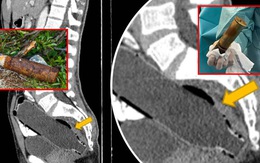

Cụ ông nhập viện với quả đạn pháo trong... trực tràng

Lực lượng tháo gỡ bom mìn được huy động, bệnh viện buộc phải sơ tán giữa đêm khi một cụ ông xuất hiện với một quả đạn pháo trong trực tràng. Một quả đạn pháo khá là... ố dề luôn đó bà con?!